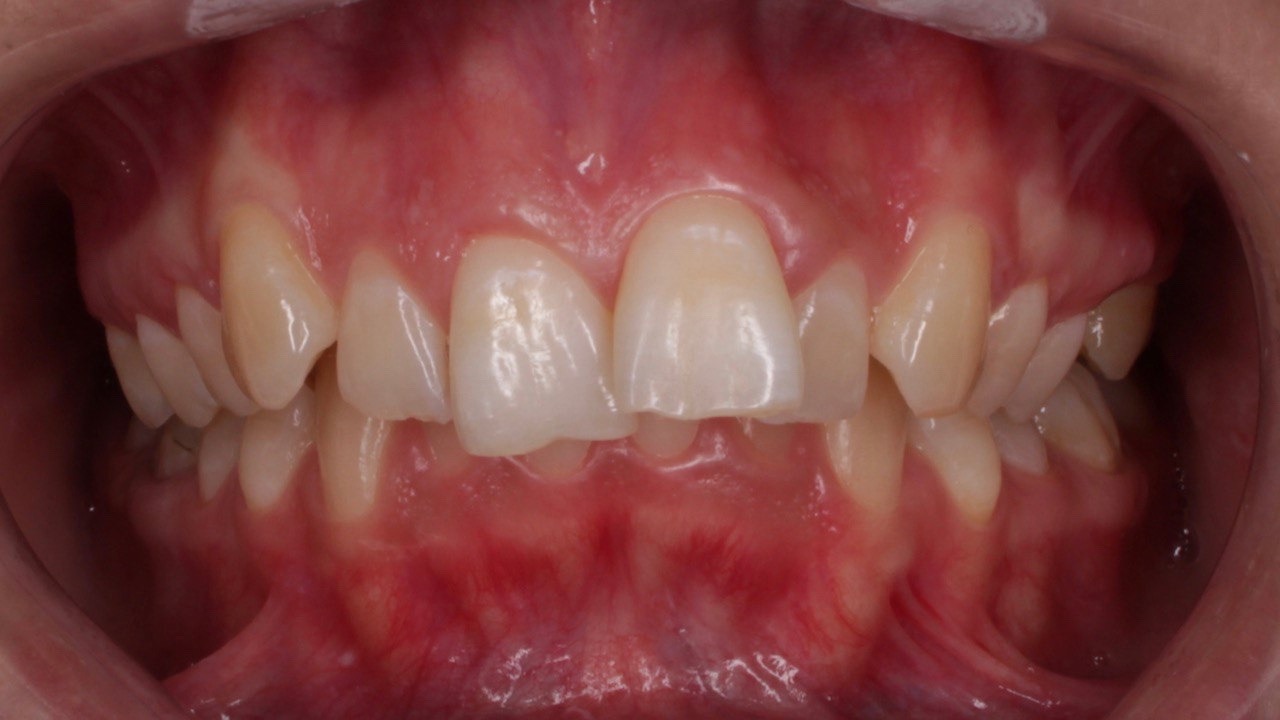

Портфолио - до 1